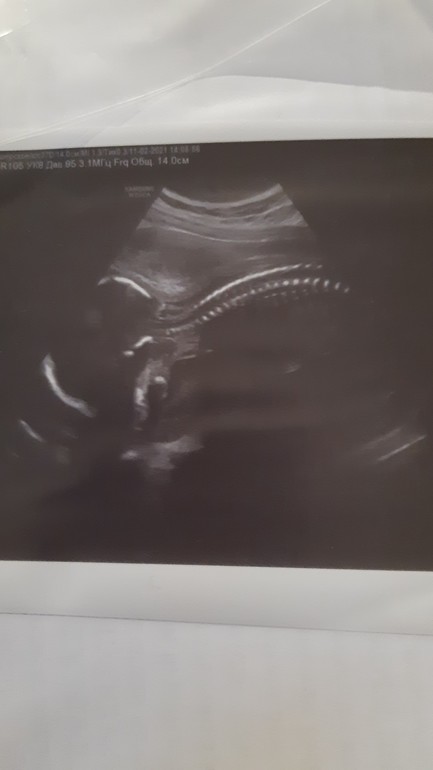

Прошли сегодня второй скрининг 💙

Мальчик остался мальчиком)🥰только и показывал своё достоинство всё УЗИ, ноги в разные стороны, мол *любуйтесь*...😅🥰

на УЗИ решил лицо своё и профиль не показывать, врачу не удалось посмотреть кости лица и тд)🥺☺ обидно, малыш отвернулся и спал)

Вес наш 317 грамм, малыш соответствует сроку, всё хорошо) 🙏🙏🙏

На первом скрининге шейка матки была 37, сейчас 29 (но врач сказал почти 30 можно написать что 30). В результате написано норма, поэтому особо не переживаю,

кроме вот такого фото врач ничего не смог предложить, сказал малыш *лентяй*, возможно в следующий раз будет по разговорчевее)))))😅😅😅